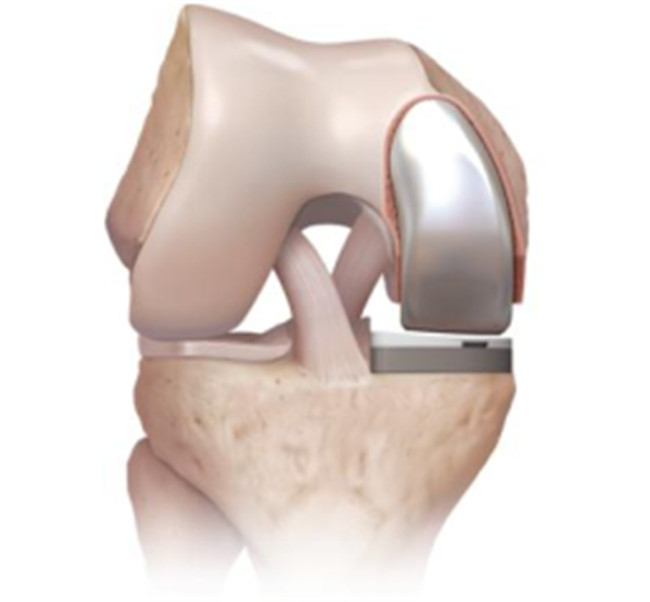

對于全膝關節(jié)置換術(shù)而言,膝關節(jié)單髁置換術(shù)是相對微創(chuàng)手術(shù),精準置換病損部位,用以替代膝關節(jié)股、脛關節(jié)損壞的軟骨表面和半月板,被稱為膝關節(jié)置換中的“補牙技術(shù)”,不需要去除前后交叉韌帶,最大限度保留病人的本體感覺和關節(jié)功能,實現(xiàn)膝關節(jié)置換手術(shù)的生理性重建。膝關節(jié)單髁置換手術(shù)具有損傷小、術(shù)后恢復快、手術(shù)外表美觀和住院時間短等優(yōu)點,是治療膝關節(jié)骨關節(jié)炎的理想辦法。目前,單髁置換技術(shù)是關節(jié)外科發(fā)展方向之一,隨著手術(shù)器械的發(fā)展和認識水平的提高,單髁置換術(shù)在臨床將會擁有廣泛的應用前景。

羅軍主任表示:膝關節(jié)單髁置換術(shù)(unicompartmental kneearthroplasty, UKA)是相對全膝關節(jié)置換術(shù)而言的一種新型微創(chuàng)手術(shù),切口僅為原來的一半,且能最大限度地保留患者正常的關節(jié)部分,對患者的損傷更小,術(shù)后療效更佳,是骨性關節(jié)炎患者的一大福音。